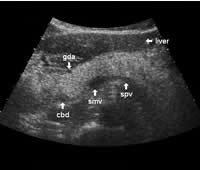

The dorsal aspect of the head takes the shape of a hook surrounding the right side of the superior mesenteric vein; the sharp left-pointing tip of the hook behind the vein constitutes the uncinate process. The splenic vein runs from the left along the dorsal border of the tail and body to the superior mesenteric vein, where these veins join to form the portal vein behind the "neck" of the pancreas. The portal vein then leaves the pancreas to the right and slightly upwards and runs into the liver hilum.

The main bile duct runs from the liver hilum to the right of and above the portal vein into the right dorsal part of the pancreatic head, where it runs vertically into the duodenum. The pancreatic duct typically runs along the body and tail to join the common bile duct near the duodenum. The gastroduodenal artery is sometimes seen in its position along the front margin of the pancreatic head, where it runs in a nearly parallel direction to the common bile duct. Like the common bile duct and pancreatic duct, however, the gastroduodenal artery is not always clearly seen due to its small diameter. The duodenum covers the right and bottom margins of the pancreatic head.

The following study describes anatomical landmarks in the ordinary pancreas of a thin patient:

Transverse planes in caudal direction: